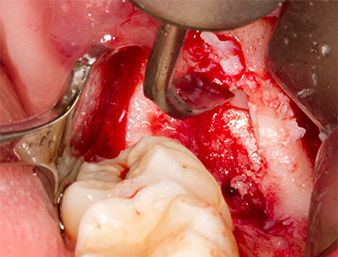

Nach Leitungs- und Lokalanästhesie wurde das Operationsfeld für einen bukkal-retromolaren Zugang weichgewebig eröffnet und dargestellt (Abb. 3).

sulkuläre Schnitt

Abb. 3: Der sulkuläre Schnitt beginnt Mitte des Zahnes 36, mit distaler Verlängerung am aufsteigenden Ast.

Das Gewebe über dem Wurzelrest war nicht vollständig verknöchert und bestand zu einem großen Teil aus entzündlich verändertem Granulationsgewebe (Abb. 4).

Granulationsgewebe

Abb. 4: Zwei Langenbeck-Haken und ein Raspatorium nach Prichard stellen das OP-Feld dar. Granulationsgewebe der unvollständig abgeheilten ersten Osteotomie ist zu erkennen.